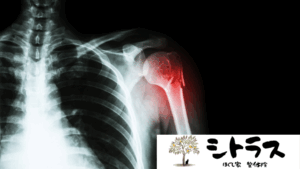

7. 病院に行くべき症状のサイン

次のような症状がある場合は、ただのぎっくり腰ではなく別の疾患の可能性があるため医療機関の受診が必要です。

- 足のしびれや力が入らない

- 排尿・排便障害がある

- 発熱を伴う腰痛

- 安静にしても改善しない強い痛み